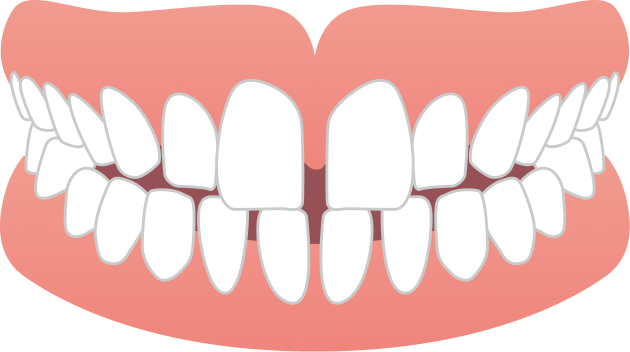

30代男性 出っ歯とガタガタが気になる

30代男性の患者さまで、上の前歯の前突感とガタつきを主訴にご相談に来院されました。目立たず、日常生活への負担をできるだけ抑えながら治療を進めたいというご希望を踏まえ、当院で専門的に行っているマウスピース矯正にて治療を開始しました。

BEFORE